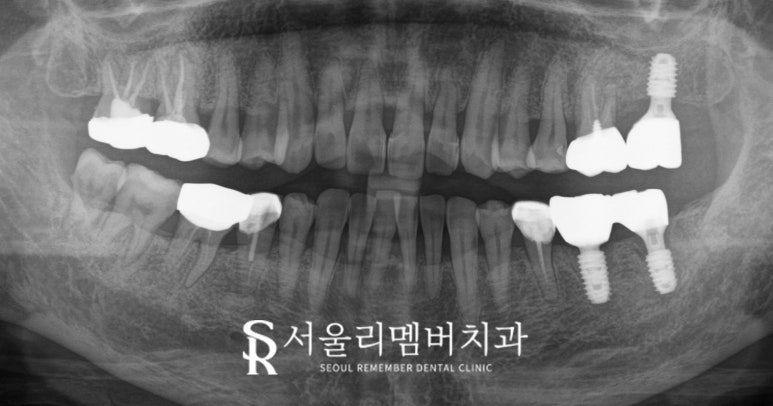

모든 과정을 마친 후 x-ray를 촬영하여

경과를 분석하는 과정은 필수입니다.

보라매 치과 에서는

안전하게 식립된 것을 확인 후

무사히 최종 진료를 마쳐드렸습니다.